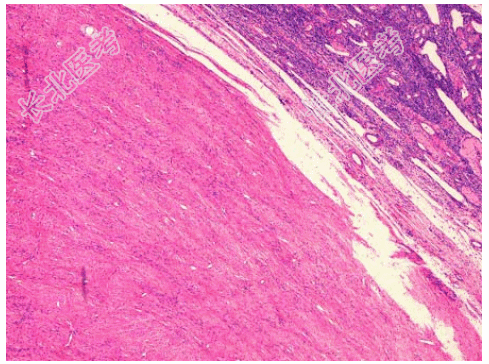

- [材料题] 患者女性,45岁,一年,腹水3月加重1月,妇检扪及左侧附件包块,质硬,行左卵巢切除送检。见卵巢一结节。直径3cm,切面灰白,略呈漩涡状。镜下见大量波浪状的胶原性结缔组织,小的梭形细胞排列成紧密的漩涡“席纹状”(如图),临床诊断为卵巢纤维瘤。

- 简答题1、该疾病镜下改变表现为?